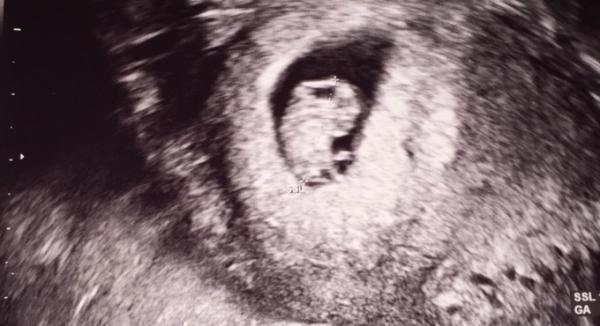

Und alles wie es sein soll. 9. Woche, ET soll der 13.01.2020 sein. Das Herzchen schlägt Leider hat mich die Übelkeit arg erwischt. Bin erstmal krank geschrieben Ich hoffe euch gehts gut!

Hier noch ein Bildchen

Supi! Da sieht man ja schon die Beinchen, oder? Wie groß ist der Krümel? Lg

Das habe ich auch schon gesagt mit den Beinchen total süß. Laut Arzt Scheitel-Steiß Länge 1,6cm